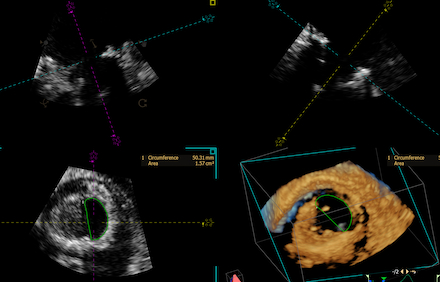

A 66 year old female with past medical history of rheumatic heart disease requiring mechanical mitral valve (MV) replacement on warfarin, HFpEF (EF 60%), atrial fibrillation requiring dual chamber pacemaker presented with worsening dyspnea on exertion. The patient was admitted for acute on chronic heart failure exacerbation requiring diuresis. Transthoracic echocardiogram (TTE) revealed significantly elevated gradients across the mitral prosthesis, concerning for significant prosthetic stenosis (peak velocity 2.4 m/s and mean gradient of 14 mmHg). Transesophageal echocardiogram (TEE) demonstrated moderate to severe mitral stenosis with a valve area of 0.6 sq cm by 3D planimetry, and poor leaflet excursion concerning for thrombus or pannus (Figure 1). Cardiac CT was suggestive of thrombus around the mechanical MV leaflets (Figure 2). Clinically, the patient had interval worsening heart failure symptoms and chest x-ray with worsening pulmonary edema. After consultation with cardiothoracic surgery, tPA was administered over 24 hours under close monitoring in the Cardiac Critical Care Unit. Repeat TEE post-thrombolysis showed improvement in MV area to 1.57 sq cm by 3D planimetry, with increased mobility of one mechanical MV leaflet (Figure 3). Persistent restriction of the other leaflet concerning for pannus remained, with no urgent surgical intervention indicated.